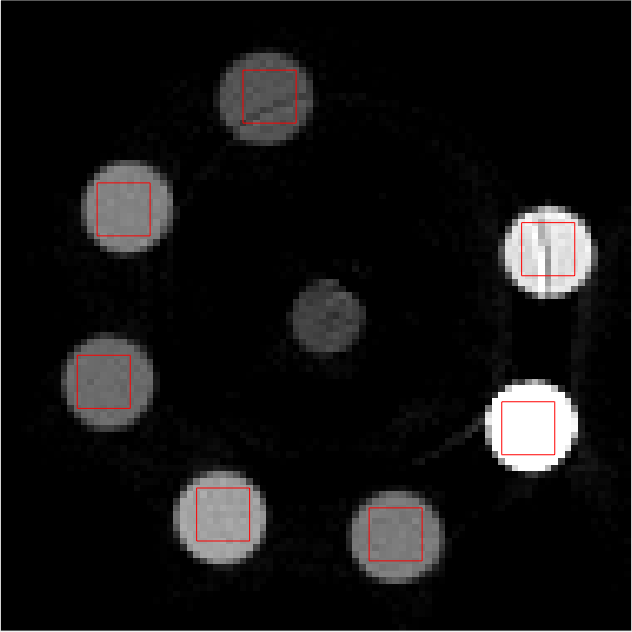

Individual reconstructions from every bin were first performed with scalar MBIR. This furnished 555 LAC images, each from a different energy bin. 101010 slices of each LAC image volume were used to compute \mathcal{M}. The mixing matrix was computed from ROIs shown in red in Fig 2. The following equation must be satisfied ideally

Refer to caption

(a)

(b)

(c)

(d)

(e)

Figure 2: Middle slice of LAC image reconstruction of each energy bin sinogram for mixing matrix estimation. Display window [0, 0.1]

LABEL:sub@fig:En1 Bin1:7.019.0keV7.019.0𝑘𝑒𝑉7.0-19.0\ keV, LABEL:sub@fig:En2 Bin2: 19.029.0keV19.029.0𝑘𝑒𝑉19.0-29.0\ keV, LABEL:sub@fig:En3 Bin3: 29.038.8keV29.038.8𝑘𝑒𝑉29.0-38.8\ keV, LABEL:sub@fig:En4 Bin4: 38.851.1keV38.851.1𝑘𝑒𝑉38.8-51.1\ keV, LABEL:sub@fig:En5 Bin5: 51.182.6keV51.182.6𝑘𝑒𝑉51.1-82.6\ keV